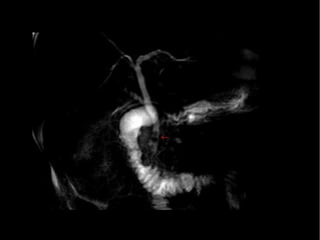

ColangioRM

• Diagnostica la causa y nivel de la obstrucción

• Buena intensidad de señal con la bilis

• La dilatación biliar se diagnostica en 97 a 100% de

los casos

• La estenosis de la VB y la coledocolitiasis se

distingue 87%

Pande H. L: bile duct. E medicine Journal. 2002,3 : 1-30.

Diagnóstico